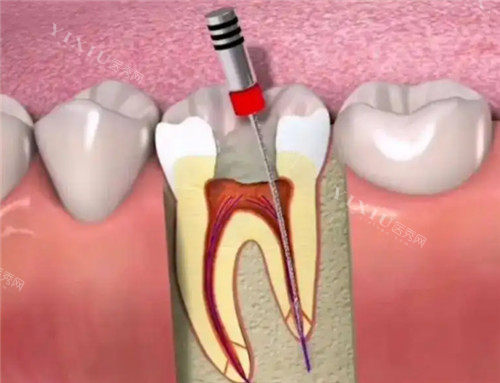

没过多久,我就见到了给我治疗的张医生。他仔细查看了我的牙片,又用工具检查了牙齿的情况,随后很耐心地跟我说:“你这牙髓已经发炎了,得做根管治疗。别担心,现在的技术很成熟,过程不会太难受的。” 接着,他拿出一个牙齿模型,边比划边给我解释根管治疗的步骤,就像和朋友聊天一样,把复杂的知识说得明明白白,让我心里有了底。

治疗过程中,比较让我惊讶的是他们用的设备。张医生操作着智能化根管治疗仪,旁边的屏幕上能清楚看到牙齿内部的情况。“你看,这就是发炎的牙髓,我们现在把它清理干净。” 看着屏幕上的画面,我心里不再像以前看牙时那样充满未知的恐惧,反而觉得有点新奇。整个治疗过程,张医生和护士配合得特别默契,每进行一个步骤,都会提前告诉我可能会有什么感觉,让我做好准备。